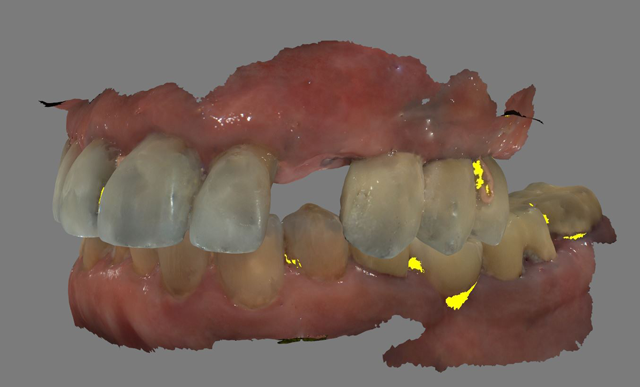

A 61-year-old male presented to my office with a fractured maxillary left canine. His past medical history was significant for previous DVT for which he was taking Coumadin. He has no known allergies (Fig. 1).

Fig. 1 Fig. 2

A CBCT scan was taken with a Carestream Dental CS 9300 (Figs. 2 and 3) and an intraoral scan was obtained using a Carestream Dental intraoral scanner (Figs. 4 and 5).